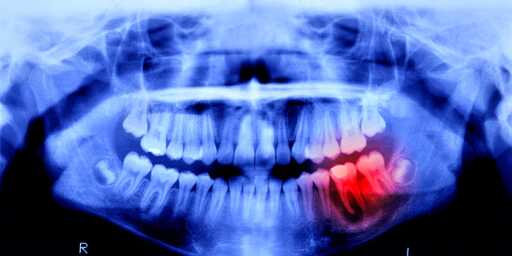

It’s the same study that’s been in process for about a decade. It entered human trials last year with those trials expected to take 5 years. Growing teeth is slow. It’s not really being pushed, it’s just the same reliable hit for various news sites to break out on slow news days.

Teeth has got to be one of the most disrespected and undervalued parts of your body. Your body’s other bones can heal but then it’s like “fuck your teeth, I’m not doing shit about them”. And then we got health insurance companies who have the gall to not consider teeth an important part of your body that should be covered, got to get it separately and the costs are fundamental.

I mean, you smile with these things and they are key responsible for how you digest food, by chewing on it before swallowing. You can’t just swallow whole pieces of food without risk of choking on them at somepoint.

You can pretty much die from bad teeth, like rot and cavities. It is just a matter of when.

A tooth infection can easily spread to your brain and kill you. It’s a very short path.

Not only does it need to become possible, it needs to become more effective than other treatments like crowns and implants. I think it’s going to be a long time, and even then will only be applicable in limited cases for a long time, and will be really expensive.